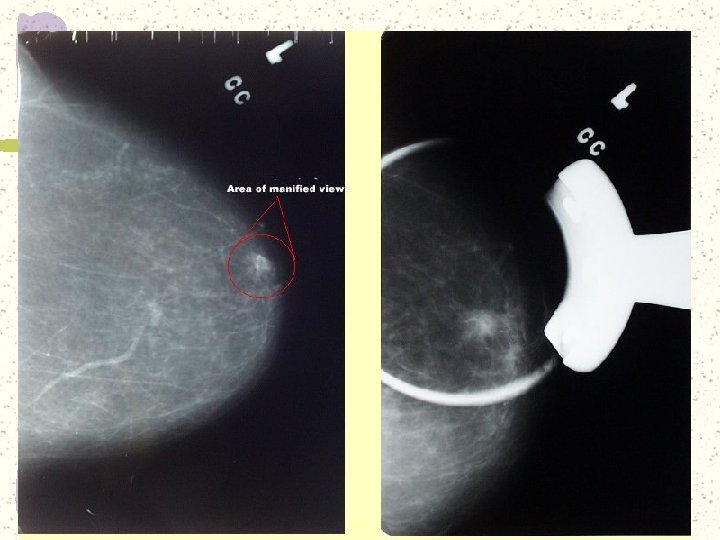

Spot Compression Used when there is a question of a mass. Tissues spread more

Spot Compression Used when there is a question of a mass. Tissues spread more evenly, possibly eliminating pseudo mass. If seen on both views, “spot” on both

Spot Compression Procedure Locate mass on CC and MLO Measure with ruler or finger

Spot Compression Procedure Locate mass on CC and MLO Measure with ruler or finger from nipple to area of interest. Measure from medial or lateral side on CC Measure from superior or inferior on MLO

http: //sprojects. mmi. mcgill. ca/dir/mammography. html